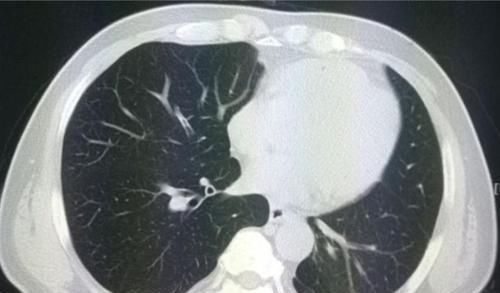

我们观察她的CT片,在她的右肺下叶有一个肺大泡(黄色箭头),紧挨着胸膜,由于气流冲击被顶破了,肺里的气体进入胸腔发生气胸。

但我们同时又有一个意外的发现:橙色箭头是一个肺结节,

结节外侧有胸膜牵拉,内部可以看到支气管充气征,综合分析符合一个高分化腺癌的CT表现。

这个小肿瘤没有症状,可以通过胸腔镜微创切除,手术后5年生存率接近100%。

但如果没有这个气胸发作,拖个一年半载的,等出现肺部症状再来,就不好说了。